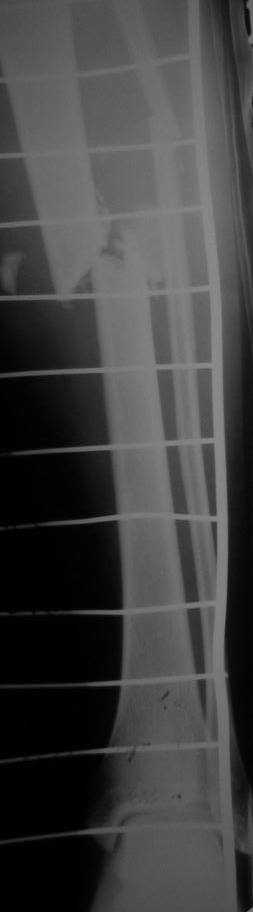

больная Ч. 24 года. Поступила в отделение после ДТП 15.01.08 при поступлении о/с костей таза АВФ. О/с лев плечевой кости спицами. На данный момент состояние больной ближе к удовлетворительному. С переломом костей голени особых вопросов нет. Хотелось бы услышать ваше мнение.